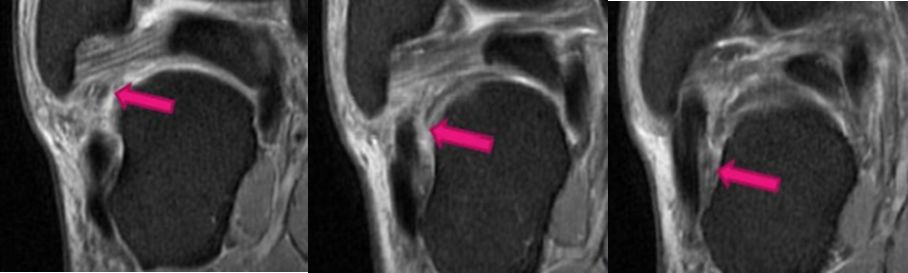

3.三角韧带:胫距前韧带、胫距后韧带、胫跟韧带、胫舟韧带

三角韧带撕裂